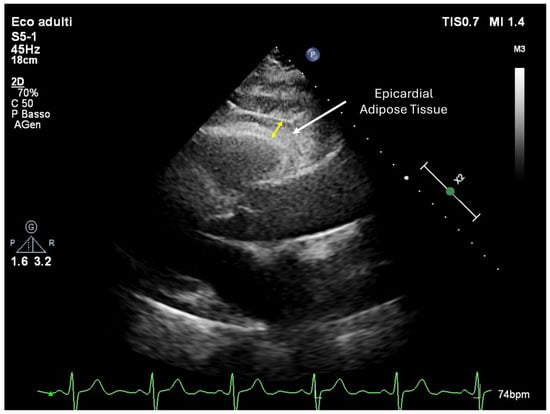

EAT is a unique visceral fat depot located between the myocardium and the visceral layer of the pericardium (Figure 2) [10]. Unlike subcutaneous fat, EAT shares the same microcirculation as the myocardium, enabling direct metabolic and paracrine interactions. Its composition includes adipocytes, inflammatory cells, fibroblasts, and abundant vascular structures [11]. Among its adipocytes, a subset resembling brown adipose tissue exhibits thermogenic properties through uncoupling protein-1, which facilitates energy dissipation as heat [12]. While brown adipose tissue is generally considered beneficial due to its role in energy expenditure, its contribution to cardiac pathophysiology within EAT warrants further exploration [13].

Figure 2.

Transthoracic echocardiography in parasternal long-axis view showing epicardial adipose tissue (arrow). The yellow arrow indicates the epicardial adipose tissue thickness.